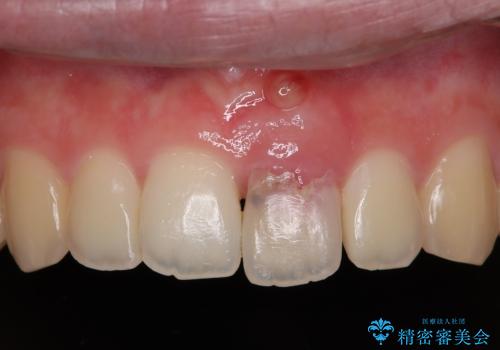

- 精密根管治療

- 2012~2025年6月

- 000歯

最新の症例

Latest cases